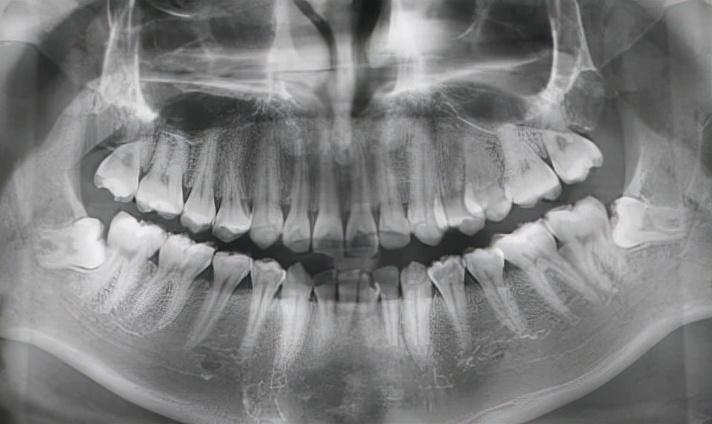

① 拔除完全長(zhǎng)出的上頜智齒,難度系數(shù):★★

垂直生長(zhǎng)的上頜智齒一般比較好拔。

像這類比較“聽話”的智齒,一般來說手術(shù)時(shí)間比較短,十幾分鐘基本上就可以搞定。

上頜智齒垂直生長(zhǎng)

② 拔除完全長(zhǎng)出的下頜智齒,難度系數(shù):★★

下頜智齒根據(jù)個(gè)人不同情況,拔牙的難度也各不相同。

垂直長(zhǎng)出的比較好拔,跟上頜智齒拔牙操作起來差不多。這兩種拔牙手術(shù)的難度都不太大,

因此手術(shù)價(jià)格也不高,術(shù)后愈合也快。

下頜智齒垂直生長(zhǎng)